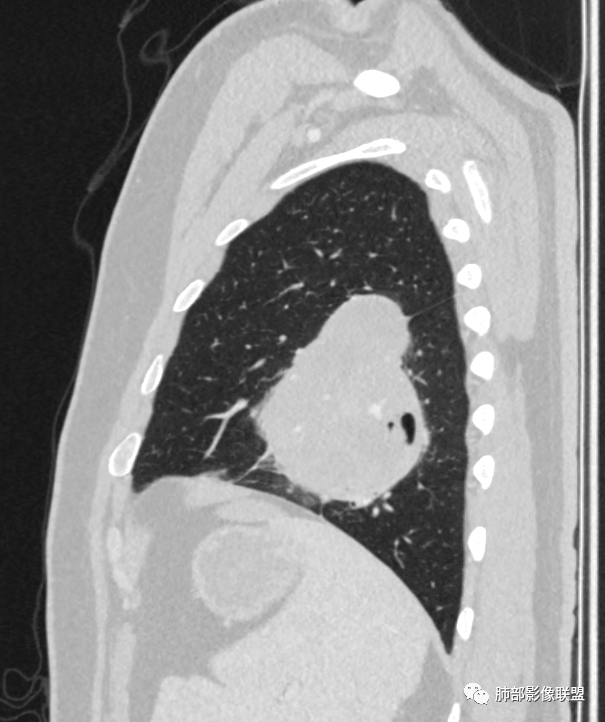

骑跨在斜裂上

局部斜裂稍增厚

青年男性,体检发现左肺不规则类圆形占位性病变,叶间裂区域,定位胸膜来源。左肺下叶支气管受压狭窄,但管壁光整,未见腔内阻塞或管壁受侵。包块边界清晰,浅分叶,内部密度不均匀,病灶后份见空气新月征。渐进性强化,增强动脉期见分支状血管,蛇纹血管征。肺门纵膈未见增大淋巴结,符合孤立性纤维瘤(SFT)。

3)肺部SFT好发于肺表面如叶间裂等区域,定位相当重要。肿块边界清楚光整,支气管不受侵(或可受压推移)。CT平扫肿瘤多呈等或稍低密度。发生于脑膜的SFT平扫肿瘤多为略高密度病,类似脑膜瘤;肿瘤较小者密度均匀,较大者内部密度常不均匀、见多发灶性或不规则形中心低密度区(细胞稀疏区含有丰富胶原纤维易发生黏液样变性或囊性变),钙化少见。